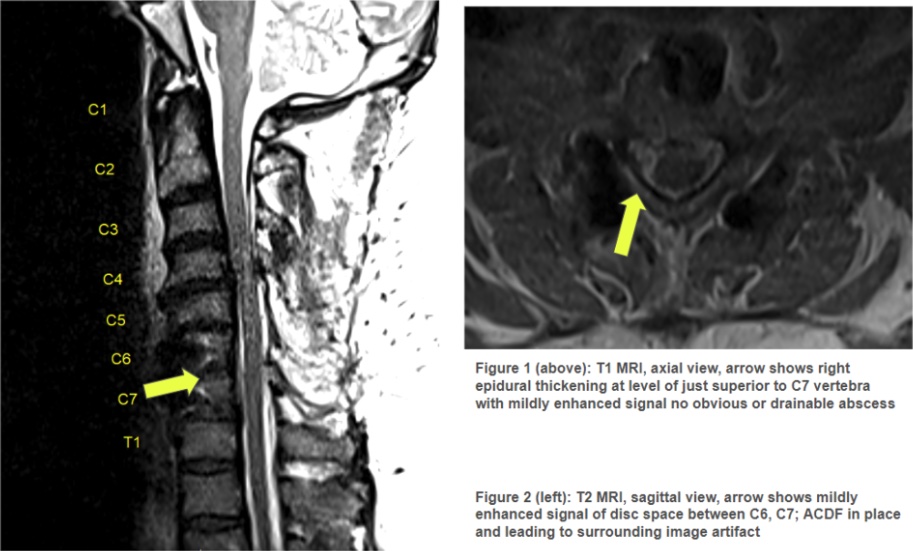

Case Presentation: A 55-year-old man with a history of obesity, gout, and multiple cervical spine surgeries, including a remote C4 laminectomy, C6-C7 fusion, and anterior cervical discectomy and fusion (ACDF) at C5-C7, presented for a higher level of care due to septic arthritis in his right knee. His medical history also included prolonged courses of methylprednisolone for chronic neck pain. At the referring hospital, knee aspiration revealed septic arthritis, prompting transfer. On arrival, orthopedic surgery performed an incision and drainage (I&D), and the patient was empirically started on vancomycin and cefepime. On postoperative day 1, blood cultures from the outside hospital showed gram-positive cocci in 2/2 bottles, and synovial fluid cultures grew Streptococcus equi subspecies equi. Antibiotic susceptibility testing confirmed sensitivity to ceftriaxone, leading to the de-escalation of therapy to ceftriaxone 2 g every 24 hours. Further history revealed indirect exposure to horses: the patient lived near a horse farm, and his dog frequently interacted with the horses before spending significant time indoors with the patient. This indirect contact was deemed the likely route of infection. Further evaluation for bacteremia revealed no vegetations on transesophageal echocardiography. However, an MRI identified discitis at C5-C7. The interdisciplinary team determined he was not a neurosurgical candidate, and he was recommended continuation of IV antibiotics. The patient was discharged on six weeks of ceftriaxone, followed by a planned transition to oral amoxicillin 500 mg every 8 hours for three months.